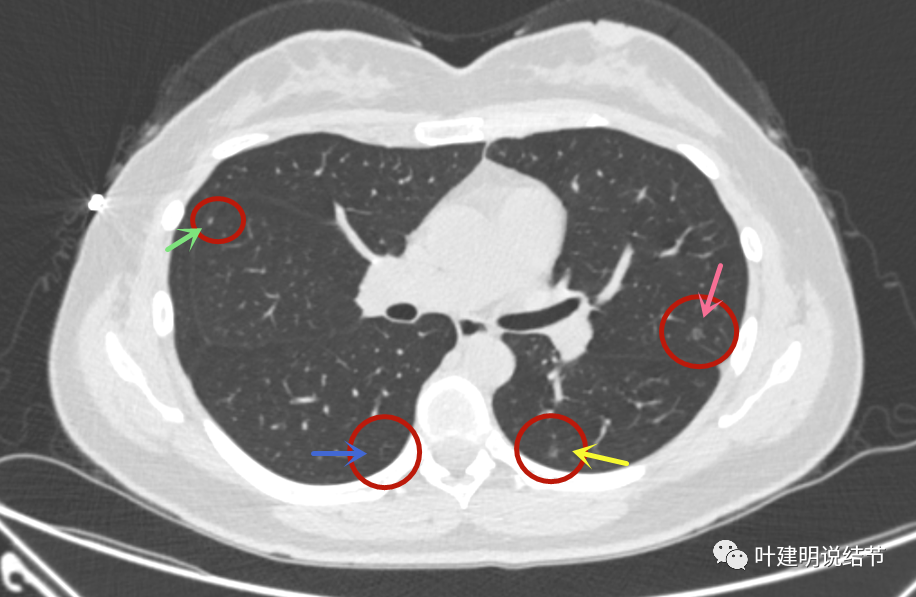

问诊仅30岁的女子两肺多达11处磨玻璃结节该干预

体检发现肺磨玻璃结节不必惊慌,建议胸外科医师随访或微创手术,一般术

单孔胸腔镜治疗多发肺磨玻璃结节

ct发现肺磨玻璃结节怎么办来听听影像医生怎么说